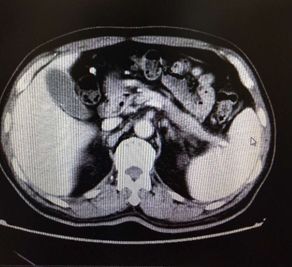

腹部CT检查结果如下:

考虑慢性胰腺炎,脾静脉血栓形成,伴脾门及胃周多发侧枝血管形成,同时合并腹主动脉夹层ⅢB型(Debakey分型),立即严格控制血压在120/80 mmHg一下,同时内科止血、输血后HGB达97 g/L转外科进一步治疗(脾切除术+胃周血管离断术以及腹主动脉支架植入术)。